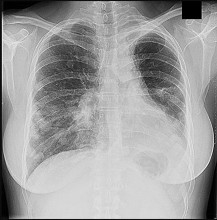

Figure 26 is the posteroranterior chest radiograph of a 76-year-old man with an atraumatic gradually enlarging mass overlying his left clavicle that has been present for 6 months. There are no changes in overlying skin. His only noteworthy medical history involves facial squamous cell carcinomas that have been successfully removed surgically.

- MRI with and without contrast_